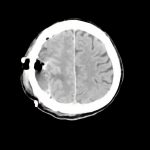

218

'21年9月

80代

左後頭頂葉腫瘤

頭蓋内腫瘍摘出術

No.’21_62 手術前1

No.’21_62 手術前2